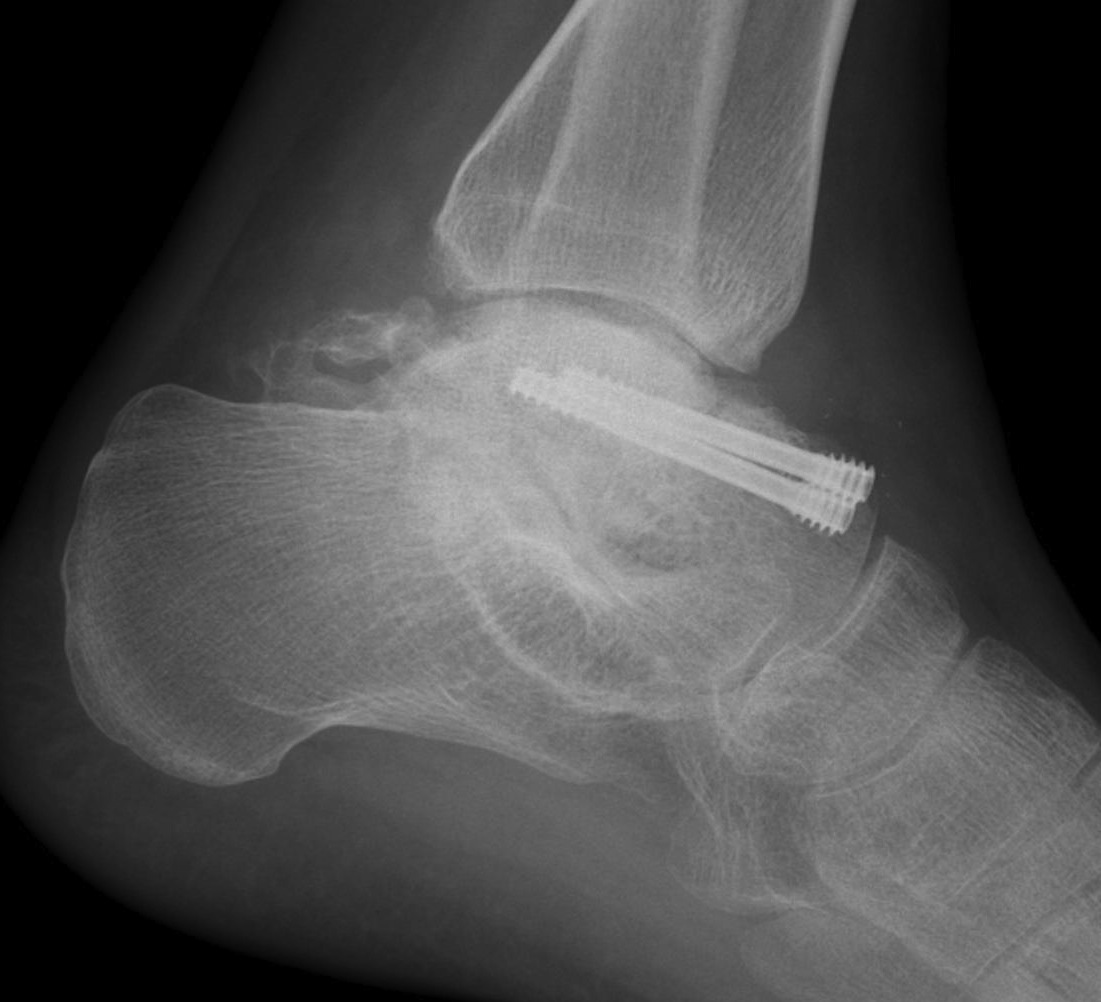

Talus AVN Post ORIFTalus AVN 1Talus AVN 2

Talus AVNtalus avn